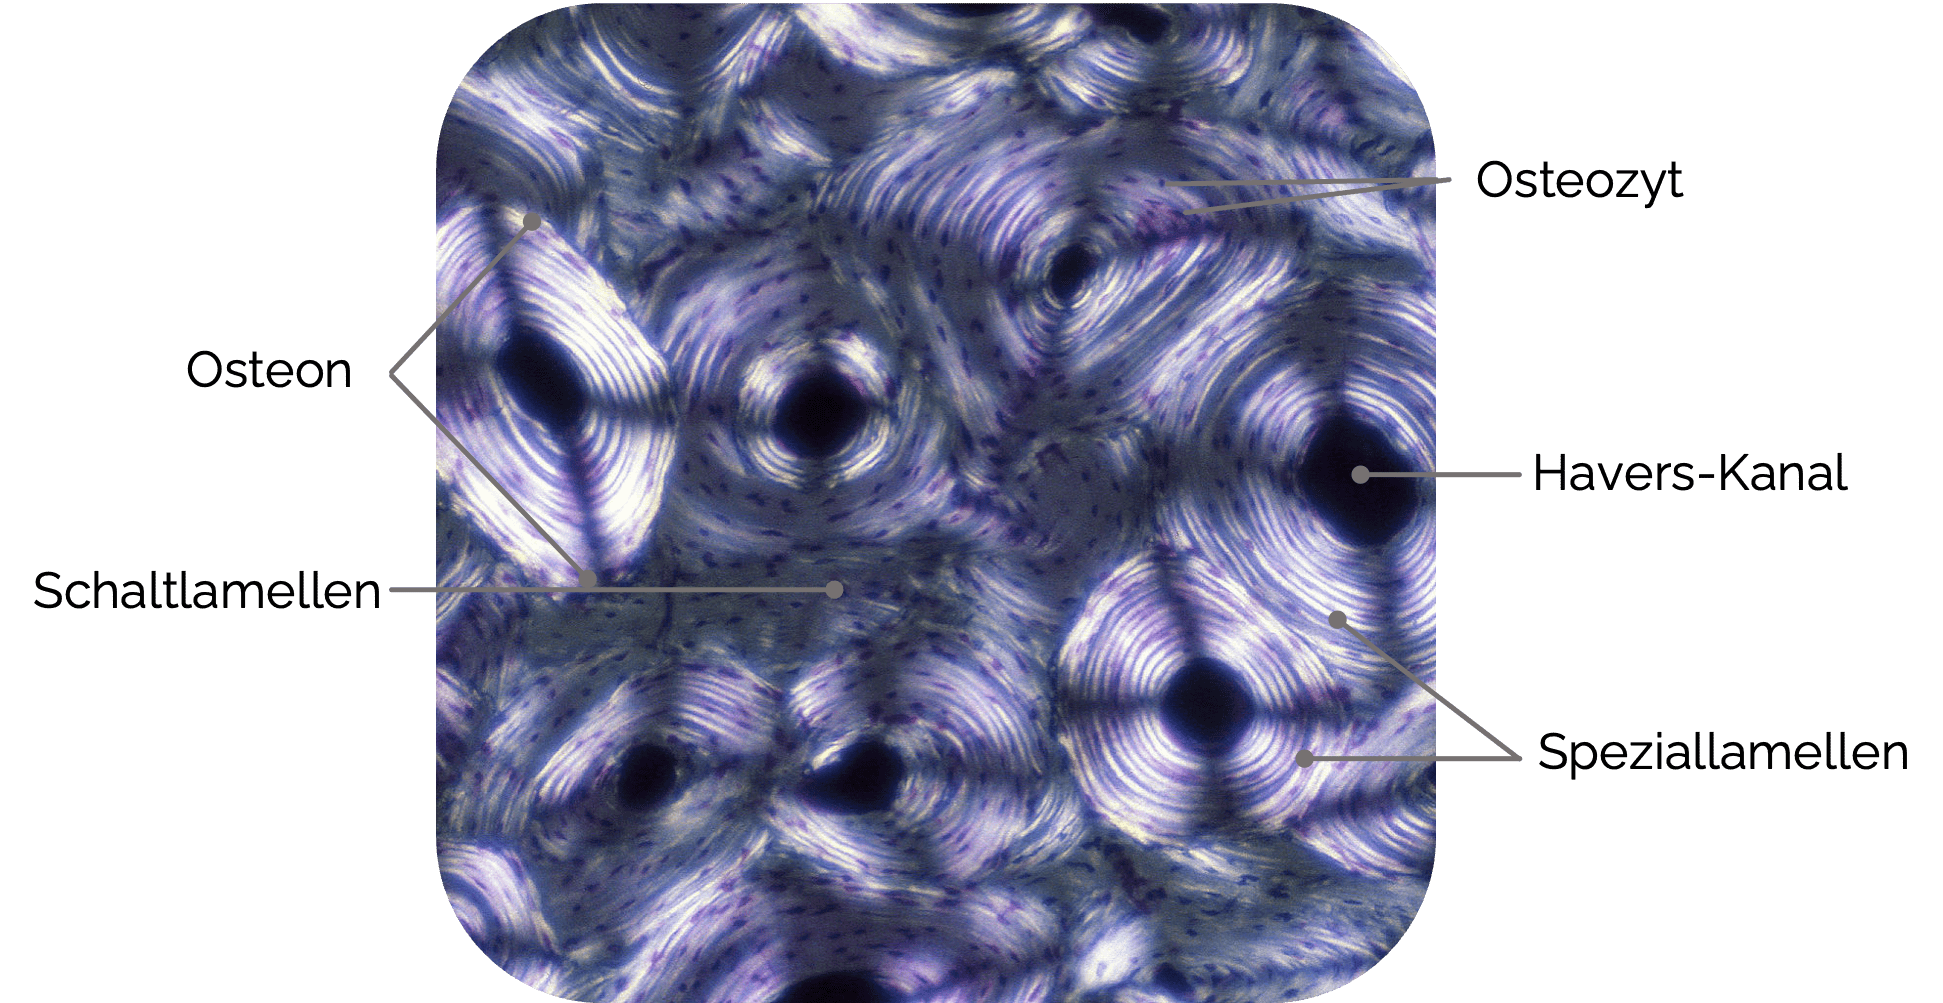

Substantia compacta (Kompakta ):

- Bestandteil des Lamellenknochens (häufigster Knochentyp)

- Bildet die äußere Knochenrinde (auch Kortikalis

genannt) unterhalb des Periosts - Die Substantia compacta

besteht aus dicht gepackten Knochenlamellen, die in konzentrischen Strukturen angeordnet sind (Osteone) - Steht mit dem roten Knochenmark der Spongiosa

in Verbindung